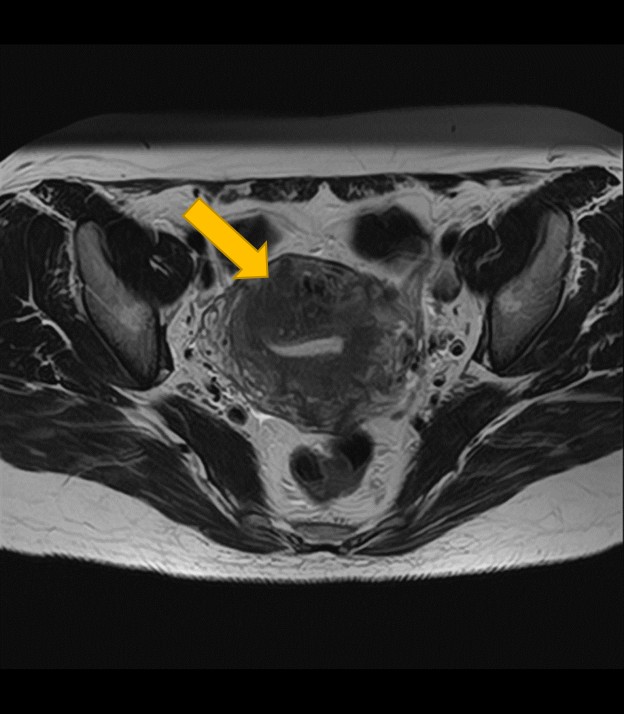

2. 卵巣腫瘍(嚢腫)のMRI:良性・悪性を判断する「中身」と「充実部分」の評価

卵巣嚢腫の中身が液体、脂肪、血液など何であるか、嚢腫壁の性状(肥厚、隔壁の有無)、充実部分の有無や血流を評価することで、良性か悪性(がん)かの可能性を判断する重要な手がかりとなります。

| 卵巣嚢腫 | 嚢腫の中身(液体・脂肪・血液など)、壁の厚さ、隔壁や充実部分の有無、内部の血流評価による良悪性の可能性。 |